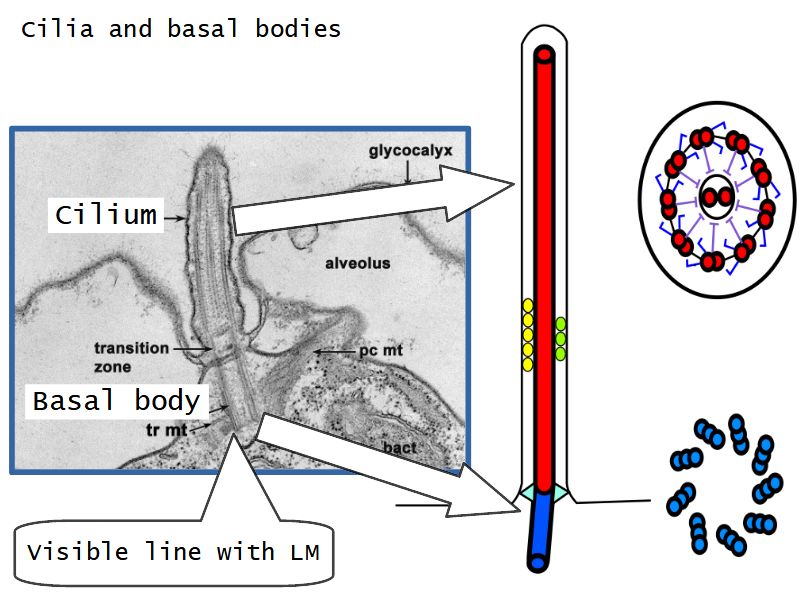

- Pseudostratified

- Ciliated

- Ciliated columnar cells

- Basal cells